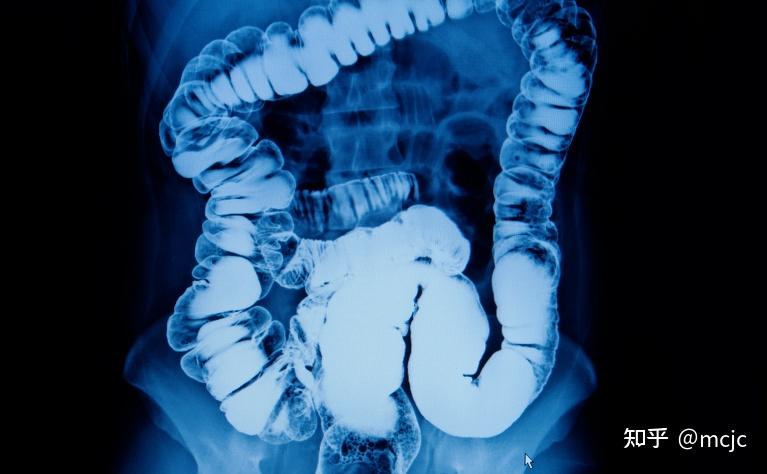

哎呀,说到克罗恩病,这可不是开玩笑的!这病啊,不仅让人肚子疼得死去活来,连带着钱包也跟着瘦了一圈。你知道吗,治疗这病的药,价格可不是一般的贵!尤其是那些特效药,一瓶下来,几千上万那是常事儿。

我这心里啊,真的是五味杂陈。每次去医院,听到药价,我的心就跟着一紧。这病不是说治就能治的,得长期抗战,药不能停。可是,这药费,真的是让人头疼。有时候想想,是不是该换个便宜点的药试试?可是医生又说,这药不能随便换,怕效果不好,病情加重。

唉,生活不易啊,得了这病,更是难上加难。每次看到账单,心里就默默祈祷,希望药价能降一降,让我们这些病人能稍微喘口气。这病啊,真的是让人心力交瘁,不仅仅是身体上的折磨,更是经济上的压力。